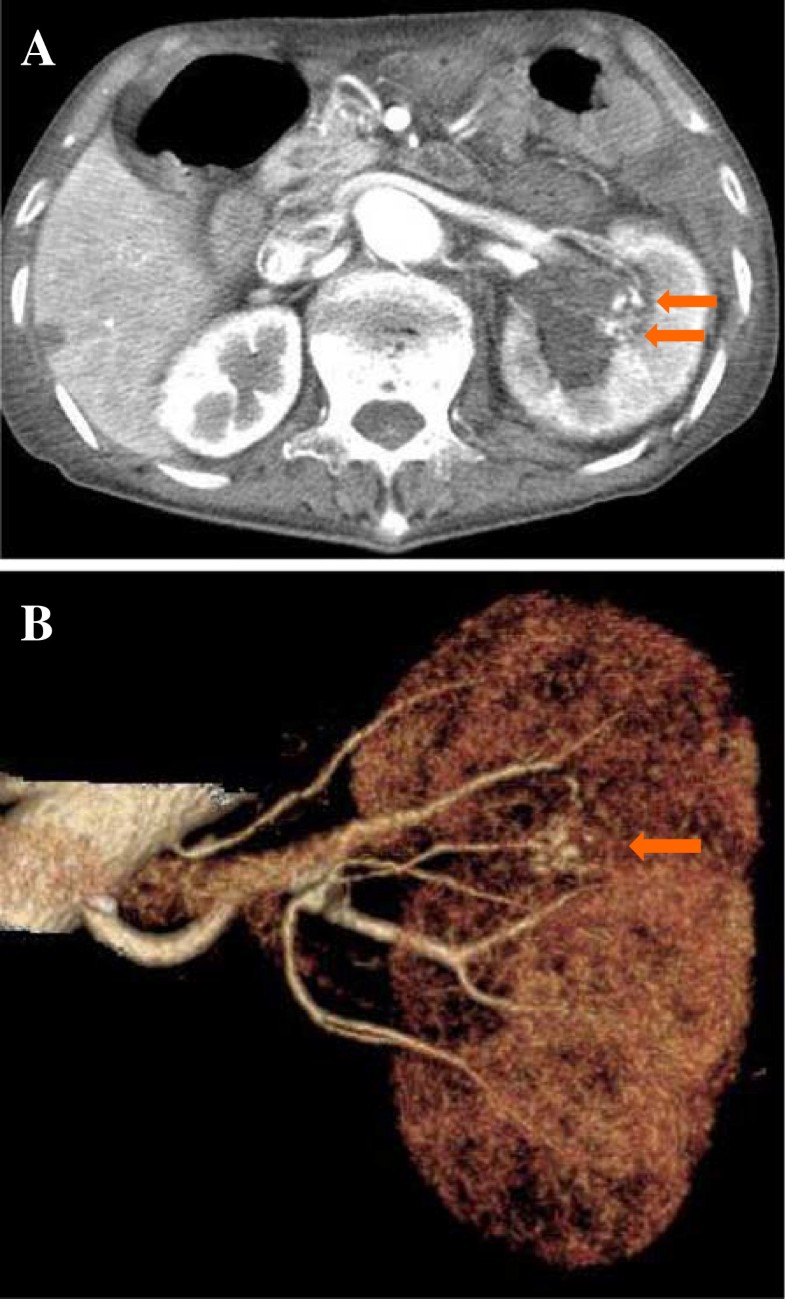

From www.fortunejournals.com

Case Report on Ruptured Renal Artery Aneurysm Can A Ruptured Kidney Be Repaired in most cases, kidney damage is permanent, but it may be possible to slow the progression of damage or, in many cases,. Perspectives of the niddk (re)building a kidney consortium. Is time of the essence? thanks to research we have funded with the wellcome trust, this study shows that in mice, kidney cells that have stopped. Acute kidney. Can A Ruptured Kidney Be Repaired.

Case Report on Ruptured Renal Artery Aneurysm Can A Ruptured Kidney Be Repaired Perspectives of the niddk (re)building a kidney consortium. in most cases, kidney damage is permanent, but it may be possible to slow the progression of damage or, in many cases,. The capacity to regenerate has mythic qualities for most of us, but the human body has. Is time of the essence? treatment can be as simple as the. Can A Ruptured Kidney Be Repaired.